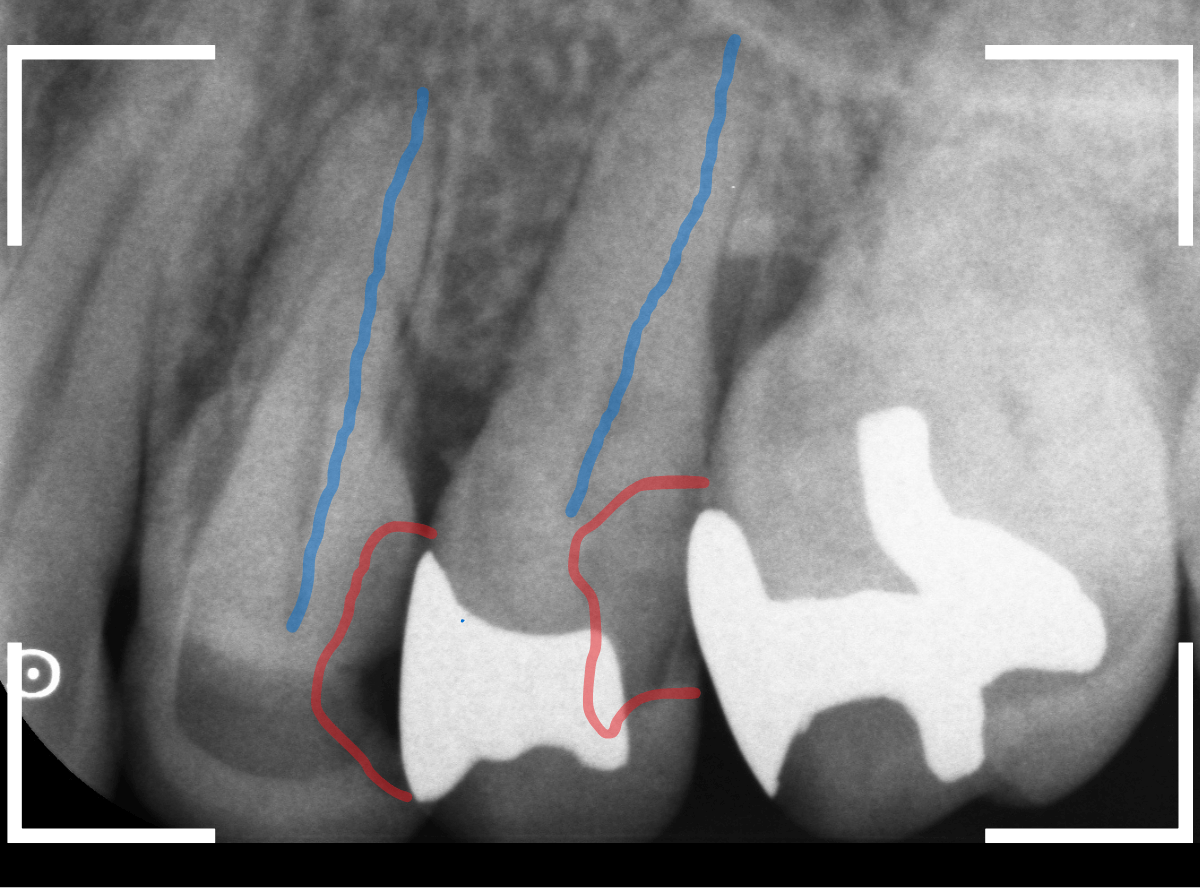

Case.21 神経に達しそうな2本の大きな虫歯

上の小臼歯の側面が明らかに虫歯になっている患者さんです。

患者さんは特に症状を感じてなさそうですが、恐らくは中で大きな虫歯になっているでしょう。

このように、自覚症状からだけでは虫歯の状況は診できません。

レントゲン写真で確認します。

青い線が歯の神経、赤い線が虫歯と思われる部分です。

2本とも、神経に達してしまいそうな大きな虫歯であると思われます。

まず、奥の歯のつめものを外してから、虫歯の治療を開始します。

手前の歯が大きな虫歯が見えてきました。

神経に達してしまいそうな虫歯ですので、ある程度削ったところで、少しずつエキスカという道具で掻き出すようにして、虫歯を除去します。

虫歯は歯を溶かして進行しますので、骨よりも固い歯もちょっと掻き出すとボロボロと崩れるようになってしまっています。

かなり虫歯を除去したところで、手前の歯は神経が顔を出してしまいました(露髄といいます)。

神経を除去する治療が必要かもしれないです。

全ての虫歯を除去したところです。

幸い、後ろの歯は薄皮一枚のところで神経まで達していない虫歯ですんでいましたが、大きな虫歯だった事には変わりありません。

いつものように、神経が痛み出さないように祈りつつ、お薬で保護して経過観察します。

虫歯は症状からだけでは判断できませんが、定期受診によって、このような大きな虫歯の処置は避けられる事がほとんどです。

かならず歯科の定期受診をしてくださいね。